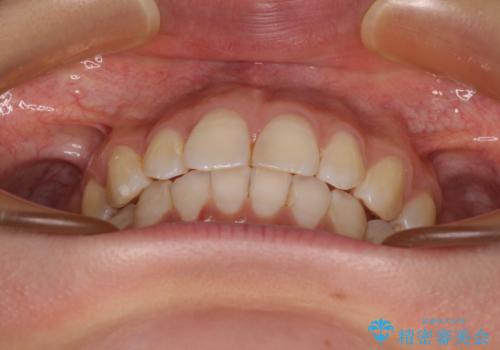

【モニター】隠れている下顎の前歯をインビザラインで改善

- 下顎の前歯が隠れていることと、デコボコを気にして来院された患者様です。

目立ちにくい装置を希望されていたため、ワイヤー装置とインビザラインを提案したところ、インビザラインを希望されました。

咬み合わせと目立っていた銀歯が改善され、患者様には大変満足していただきました。